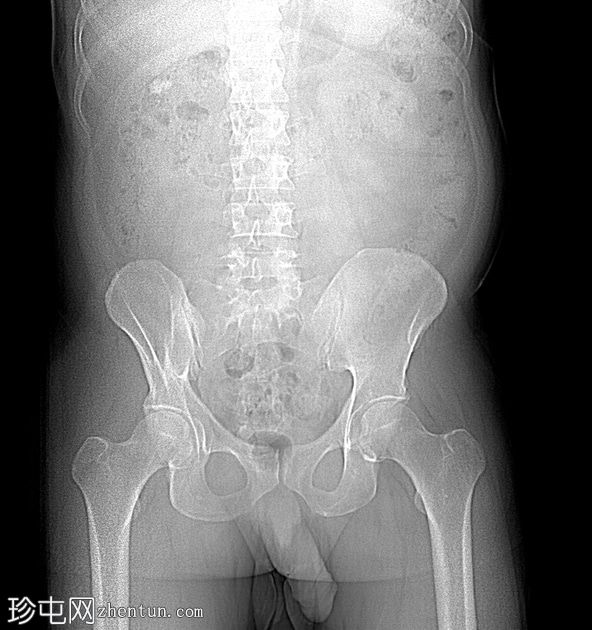

腹部平片(KUB)

前后位(AP-lateral)

右肾上盏内可见一中等大小的结石,大小约为16 x 13 x 15 mm。右肾中盏内可见一小结石,大小约为4 x 2 mm。右肾下盏内可见另一小结石(过小无法测量)。未见肾盂肾盏扩张。

非增强 CT KUB 显示右肾多发结石,其中上肾盏结石较大,大小为 16 x 13 x 15 mm,密度较高(平均约 1060 HU),符合钙结石的特征。中肾盏和下肾盏可见其他较小的结石。

肾盂肾盏系统未见扩张,提示无梗阻性病变。该发现与患者反复腰痛的病史相符,腰痛可能与结石移位有关,而非当前存在梗阻。